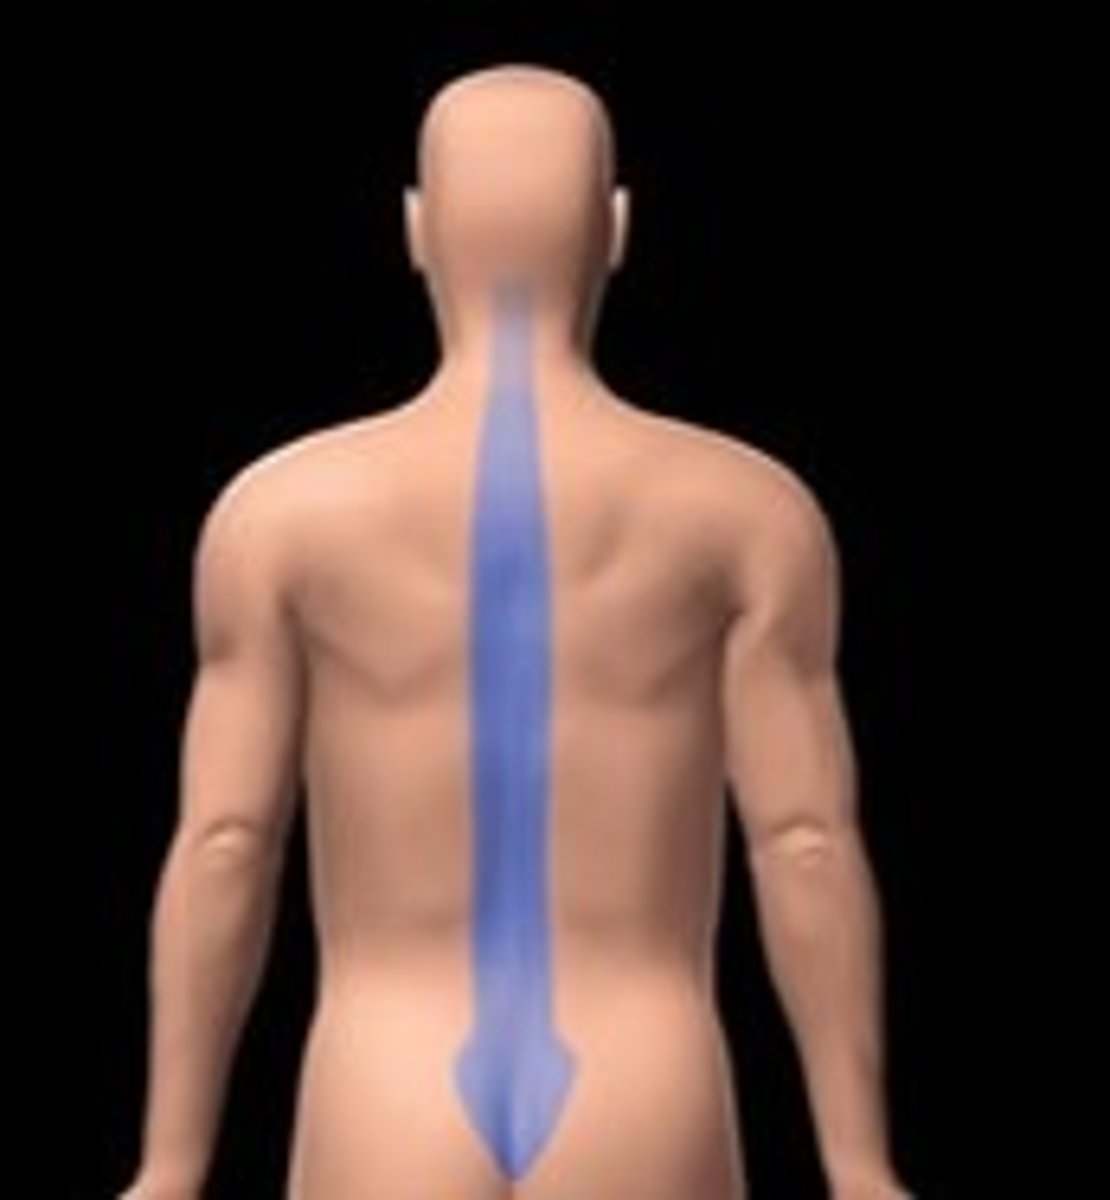

Vertebral

Area of the spinal column